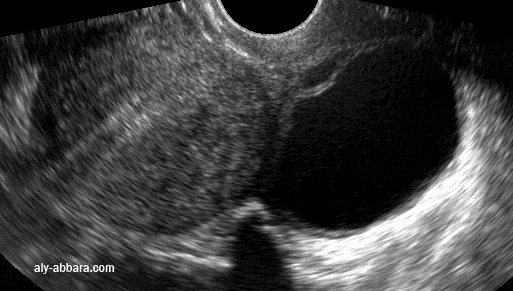

Kyste ovarien gauche  fonctionnel  qui est apparu  5 mois après la pose d'un stérilet hormonal, il s'agit d'un kyste de 50 mm de grand axe

• Image échographique montrant un des aspects de la tige verticale du stérilet hormonal (au lévonorgestrel) avec la formation d'un cône d'ombre par la réflexion des ondes ultrasons au niveau de cette tige qui est parfaitement individualisable.

• Puis l'image montre un des inconvénients du dispositif intra-utérin hormonal, il s'agit de la formations des kystes fonctionnels ovariens. En effet, des follicules augmentés de taille sont observés chez environ 12 % des utilisatrices (des kystes fonctionnels ovariens ont été observés chez 12 à 31 % des femmes). Ces follicules ne peuvent être distingués cliniquement des kystes ovariens. La plupart de ces follicules sont asymptomatiques mais certains peuvent s'accompagner de douleurs pelviennes ou de dyspareunie. Dans la majorité des cas, ils disparaissent spontanément au bout de 2 ou 3 mois. Dans le cas contraire, une surveillance échographique continue, ainsi que d'autres mesures thérapeutiques ou diagnostiques, sont recommandées. Une intervention chirurgicale est rarement nécessaire.

• Chez cette patientes, ce kyste est apparu cinq mois après la pose du dispositif intra-utérin hormonal ; il s'agit d'un kyste fonctionnel de l'ovaire gauche.